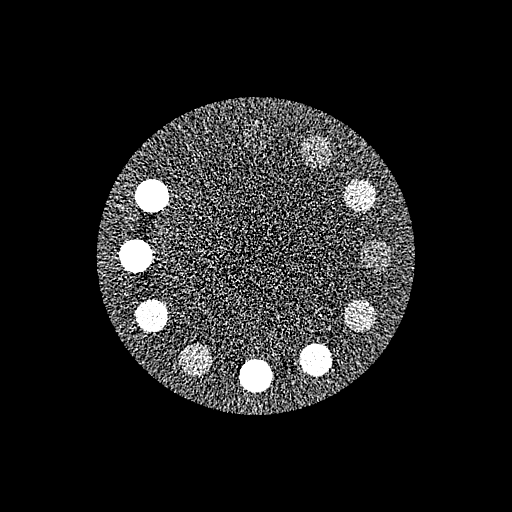

Reconstructed 35 – 85 keV Mono-Energetic Images

Ground-truth References

(20-cm cylindrical phantom)

Conventional Physics-based Mono-Energetic Images